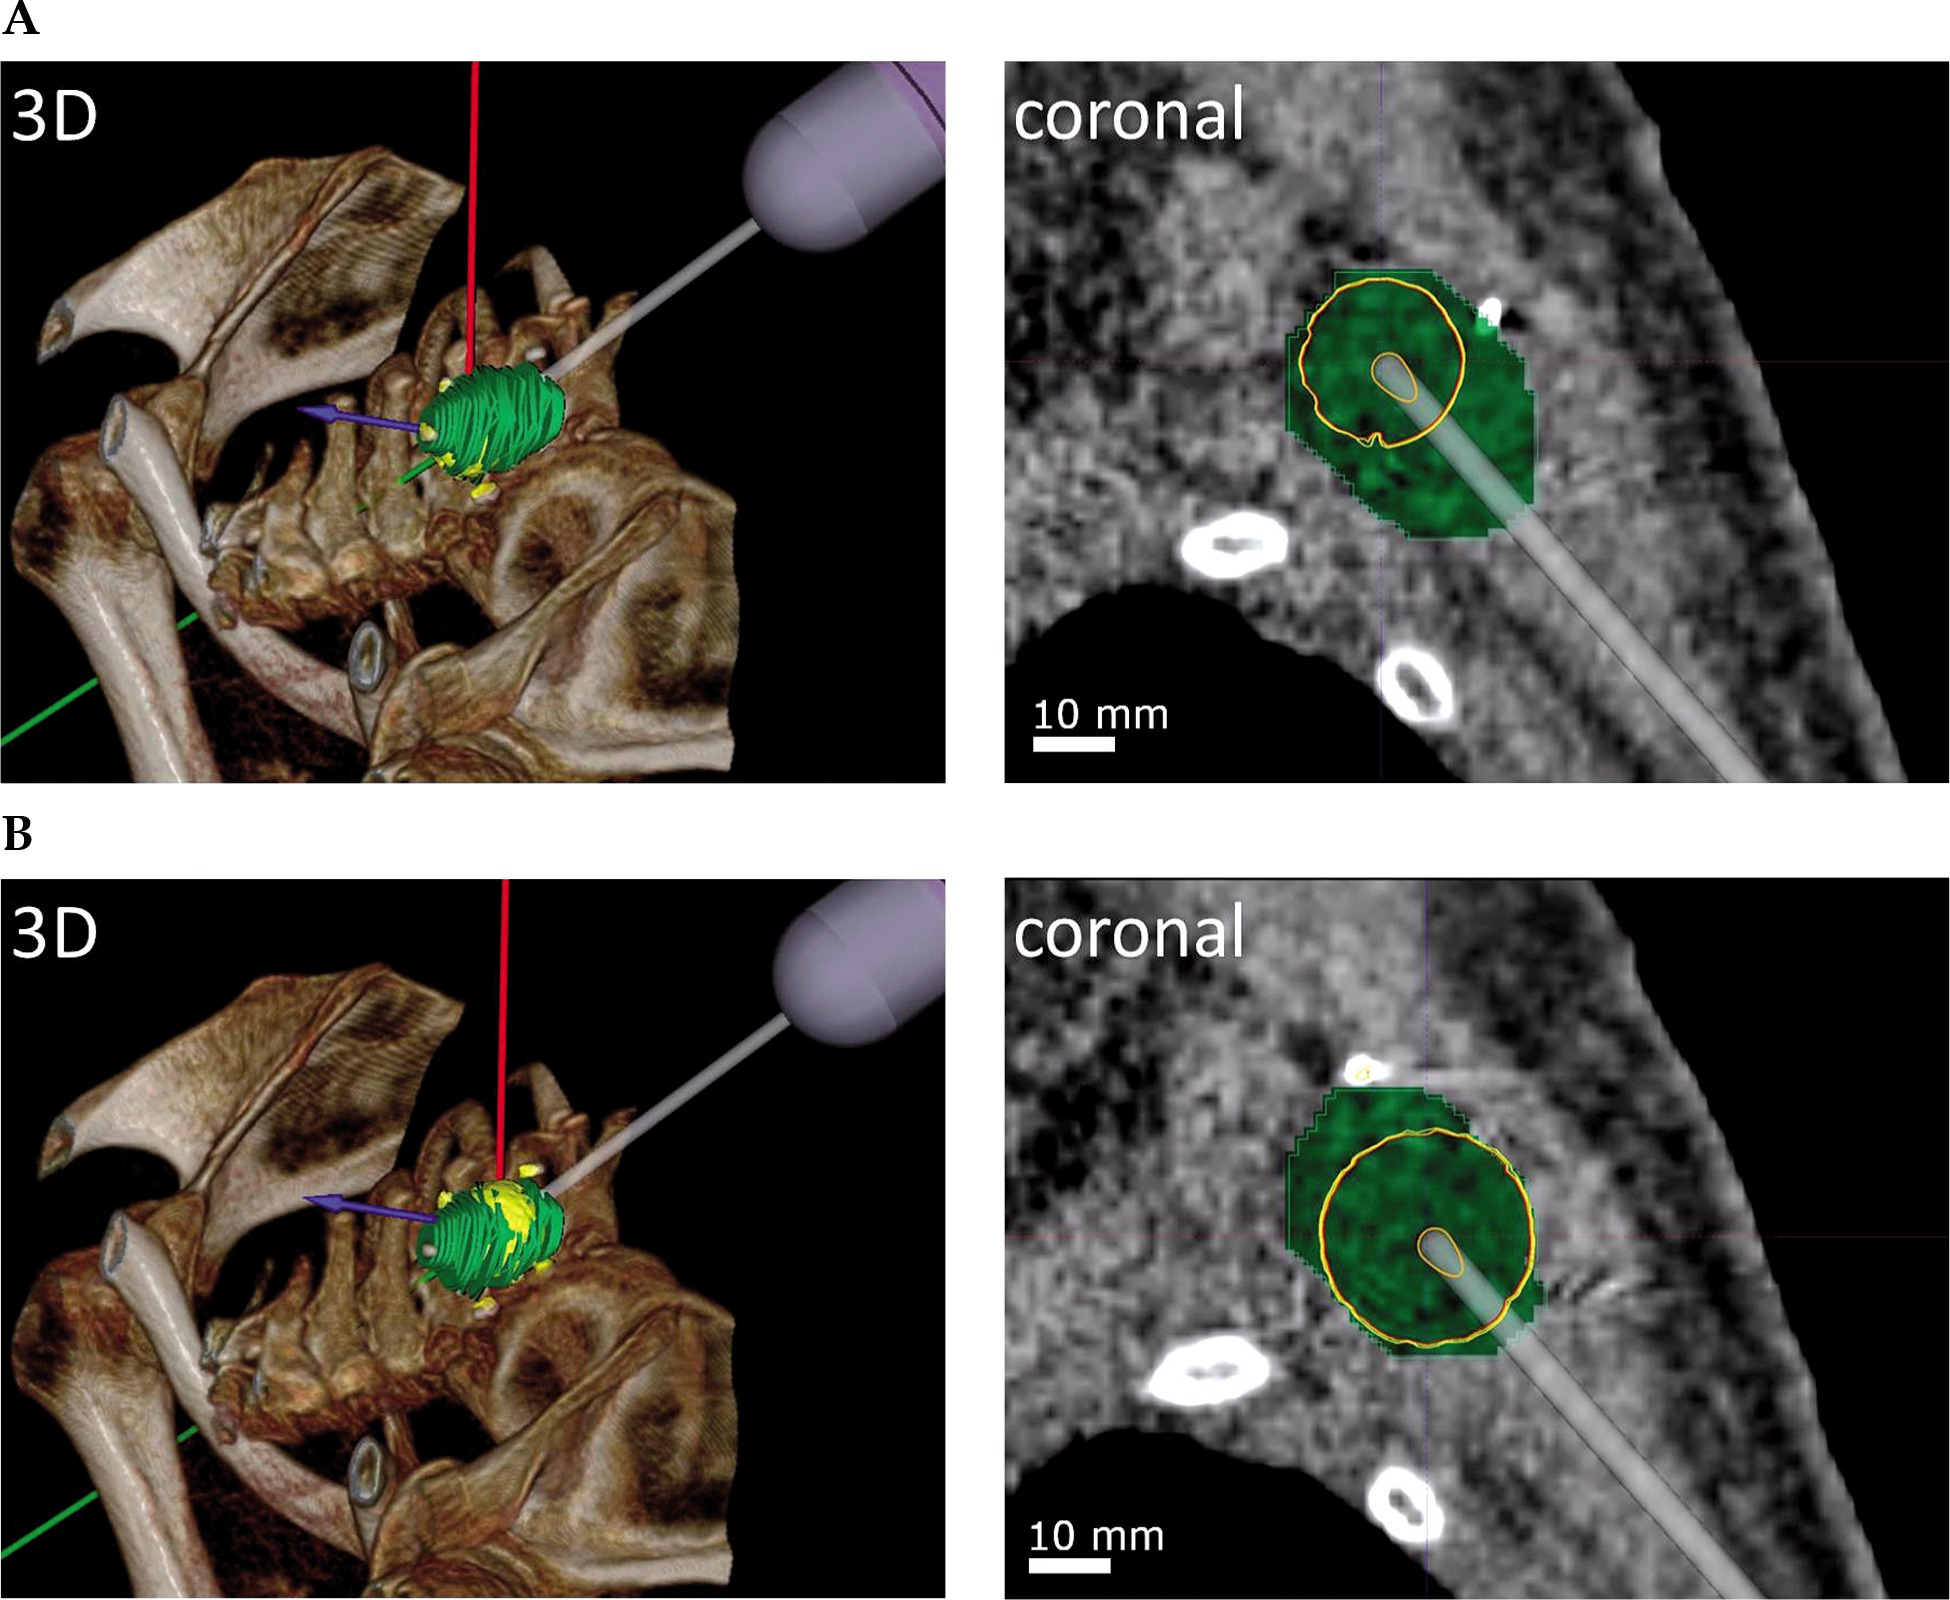

Planning

Doses were adopted from PSI and prescribed to 90% of the PTV for EBT, with a minimum of 10 Gy, a maximum of 60 Gy, and an average of 31 Gy (SD = 14.6). The average volume of PTV was 50.6 cm3 (SD = 34.5), with a minimum of 11.9 cm3 and a maximum of 106.7 cm3. The total number of iodine seeds implanted during PSI ranged between 5 and 28, with an average of 15 iodine seeds (SD = 7.6), which required between 4 and 11 needle trajectories (average, 6.9, SD = 2.2). For EBT, the total number of trajectories per case varied between 1 and 13, with an average of 5.0 (SD = 3.2). All trajectories for EBT fulfilled requirements of a realistic puncture. In comparison to PSI, the number of trajectories needed for EBT was lower in 7 cases and the same in 2 cases. In 1 case, additional trajectories were necessary for EBT. Overall significance for less trajectories in EBT could not be shown in this cohort (Mann-Whitney U test, two-tailed, significance at p ≤ 0.05, U-value = 25, Z-score = 1.85203, p-value = 0.06432). The number of utilized dwell positions for EBT ranged from 2 to 25, with a mean of 10.9 (SD = 7.1) dwell positions per case. On average, 2.1 (SD = 1.1) dwell positions per trajectory were generated, with a minimum of 1 and a maximum of 4 dwell positions. An example of the simulated needle applicator stepping along a trajectory is shown in Figure 2. On average, total forward planning time per case was 3.0 h (SD = 1.4), with a range from 0.8 h to 5.7 h. Moreover, planning time strongly correlated with the number of trajectories and dwell positions (Pearson’s correlation coefficient, r (8) = 0.94, p < 0.05, and r (8) = 0.98, p < 0.05).

Fig. 2

Simulation of the needle applicator stepping along a virtual trajectory in a lesion in the left shoulder region. The PTV (green) contains two dwell positions, with (A) dwell position 1 and (B) dwell position 2, each displayed in 3-dimensionally rendered view (3D) and in a coronal plane. The dose distributions of dwell positions are displayed as isodose lines of 90%, 95%, and 100% of the prescribed dose in yellow, orange, and red, respectively